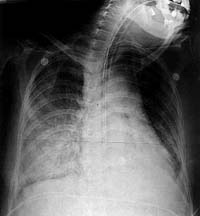

Ca bệnh đầu tiên là một đàn ông 75 tuổi, người Việt Nam với tiền sử 5 năm bị hen được kiểm soát bằng corticoides liên tục, nên điều này buộc ông ta phải nhập viện nhiều lần. Vào tháng 6 năm 1998, bệnh nhân nhập viện vào khoa cấp cứu của bệnh viện Pomona Valley Hospitalvì suy hô hấp hai ngày sau khi ông ta điều trị hen phế quản mạn tính tại đây 10 ngày. Ông ta cũng đã có kinh nghiệm trong điều trị bệnh của mình theo những cơn khó thở không còn đáp ứng với beta-agonist. Ông ta không thừa nhận có sốt, nhưng khai bệnh có các vết ngứa và dị ứng trên da vùng bụng. Thuốc được cho vào thời điểm nhập viện bao gồm prednisone (40 mg mỗi ngày), theophylline, zafirlukast, albuterol, và ipratropium/ triamcinolone acetonide cho liều có kiểm soát. Bệnh nhân có tiền sử nghiện thuốc lá 50 gói/năm nhưng không hút thuốc lá trong vài năm gần đây. Khám thực thể cho thấy bệnh nhân suy hô hấp cấp, huyết áp 190/94, có tiếng khò khè 2 bên phổi và nổi các ban đỏ dạng herpes (serpiginous erythematous rash) lên phần bụng dưới và phần trên đùi, sau khi thông khí tại cấp cứu ICU, khí máu cho trị số pH 7.17, pCO2 là 102 và pO2 là 131 trên 100% O2 không (non-rebreather mask). X-quang phổi biểu hiện tăng thâm nhiễm khoảng kẻ hai bên (hình 1,2). Giá trị xét nghiệm cho biết công thức bạch cầu 24,000 với 5% eosin, glucose máu 216. nhuộm Gram dờmthì dương tính với nhiều bạch cầu và ấu trùng giun lươn Strongyloides stercoralis (hình 3). Xét nghiệm phân âm tính với ấu trùng giun lươn, nhưng phát hiện thấy trứng của giun móc hoặc giun mỏ Necator americanus hoặc Ancyclostoma duodenale.

4 ngày sau khi phẩu thuật, bệnh nhân phát sốt và thở nhanh. Nghe phổi có ral nổ (crackles) hai bên toàn phế trường. X quang phổi cho thấy thâm nhiễm phế nang lan tỏa (hình 4). Công thức bạch cầu cho thấy 15.000 với Hb 8.2 và Hct 24.1%; cấy đờm cho kết quả vài cầu khuẩn gram dương và cấy máu âm tính. Bệnh nhân tiến triển suy hô hấp cấp và phải đặt ống cho thở máy. Khí máu cho kết quả pH 7.28, pCO2 là 40, pO2 là 105 trên70% FIO2 phải trợ thông khí. Điều trị kháng sinh phổ rộng diệt vi khuẩn kỵ khí cũng như các loại vi khuẩn không điển hình thương gây nhiễm trùng cơ hội. Mẫu bệnh phẩm đờm được nhuộm và nuôi cấy để đánh giá có khả năng là Pneumocystis, Strongyloides, Cryptococcus, hay nhiễm Mycobacterium. Phân tích huyết thanh học với kháng nguyên Cryptococal và kháng thể coccidioidal antibodies được thực hiện dựa theo quy trình sàng lọc nước tiểu đối với kháng nguyên của chủng Legionella.